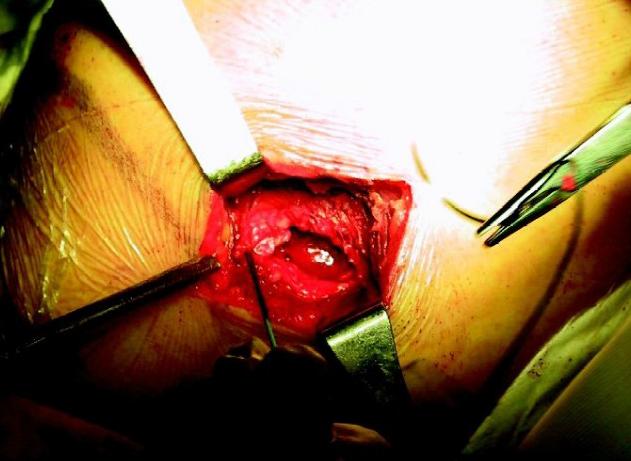

1.传统切开手术

早期的肩袖修复手术多采用切开的方式,这种手术方式必须先将肩峰外侧端或前侧端甚至全肩峰进行切除后才能进行肩袖修复术。尽管这种手术方式能明显缓解疼痛,但术后三角肌的力量会明显减弱,影响我们正常的肩关节功能。

但在关节镜技术诞生前,这一技术就是当时治疗肩袖撕裂的标准技术。

传统切开手术具有创伤大、恢复慢、无法发现和处理关节内病变等缺点。

传统开放切开手术 图片来源于网络,侵删